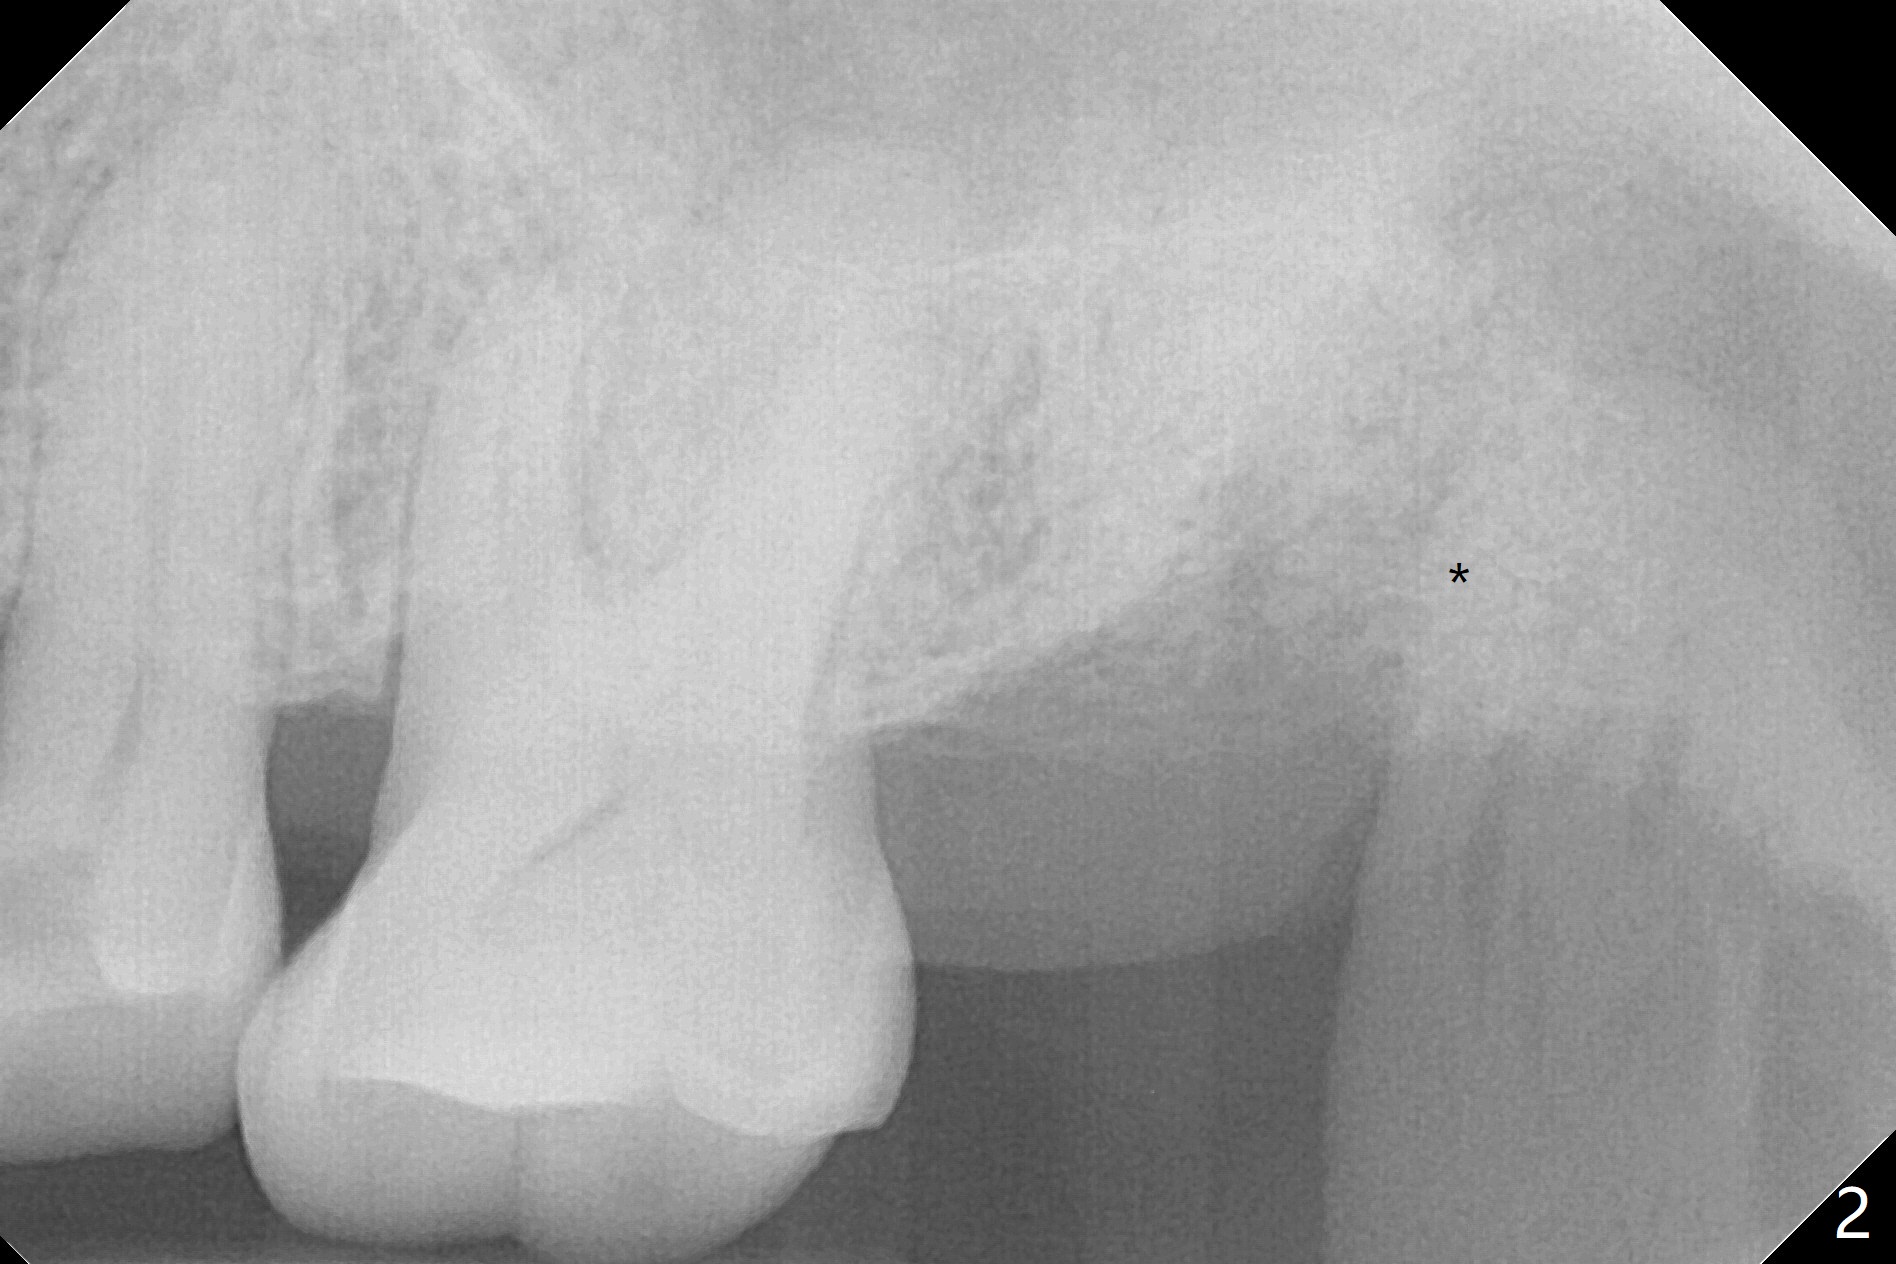

A 61-year-old woman requests #15 implant post ones at #2 and 6 because of pain in mastication (Fig.1). Examination shows that the tooth #16 has advanced periodontitis with mesial bone loss (Fig.1 *). It appears that there is insufficient bone for #15 implant. Bone graft seems necessary at #16 after extraction. There is severe hemorrhage post extraction. Osteogen plug is inserted for hemostasis prior to placement of allograft (Fig.2 *). The socket opening is covered with 12x12 mm Amnion-Chorion Membrane and 5-0 Polysyn. The socket seems to heal 9 days postop (Fig.3). The bone graft in the socket of #16 three months postop (Fig.4 *) will support an implant to be placed at #15 distal (Fig.5 *).